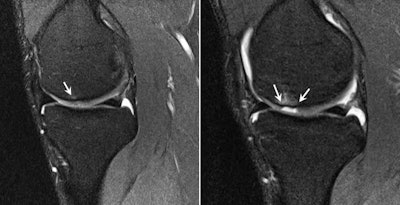

The knees are another key focus of the presigning exam due to the high load volume and biomechanical demands of the knee joint during kicking, sprinting, and direction change associated with soccer, Dunn continued.

Knee protocols include sagittal, coronal, and axial combination of high-resolution proton density fat-saturated and proton density sequences of no greater than 3-mm slice thickness. Dunn underlined that small degenerative tears in the anterior horn of the lateral meniscus may be a common subclinical finding and do not usually raise concerns for the referring clinician. However, larger, potentially displaceable tears of the posterior horns could progress more suddenly, requiring arthroscopic repair or resection and affecting an athlete's playing time.

Images often depict chronic, small, healed tears that are clinically stable. "These demonstrate intermediate signal on T2 or intermediate weighted MR sequences, and should not be misread as active tears," he wrote.